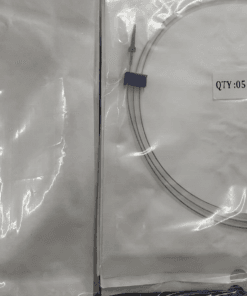

PTFE Guide Wire Set of 10 Urology Size 0.035 Length 150cm Straight

PTFE Guide Wire Set of 10 Urology Size 0.035 Length 150cm Straight

Guide wire with and without PTFE coating

- This wire is made by Galvanized Stainless Steel, and having fixed core. UROMED guide wire has excellent flexibility.

- Size: 0.035”

- Lengths: 150cm

Images are for illustration only. Company may change item design and packaging from time to time. We will ship latest stock available.